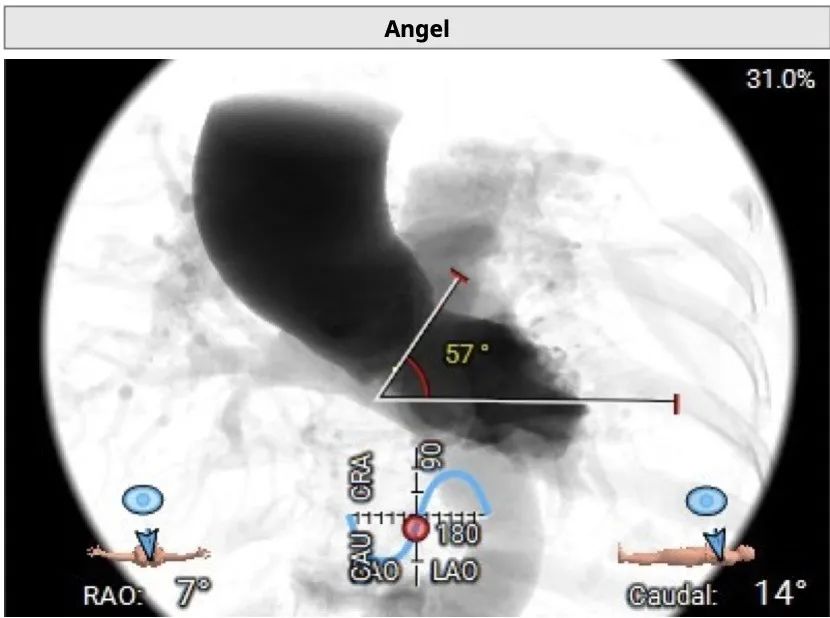

术中建议造影角度RAO 7°,CAU 14°(其它参考角度如下图):

主动脉弓、降主动脉及双侧髂总动脉见多发钙化;胸主动脉迂曲;心室角度57°: